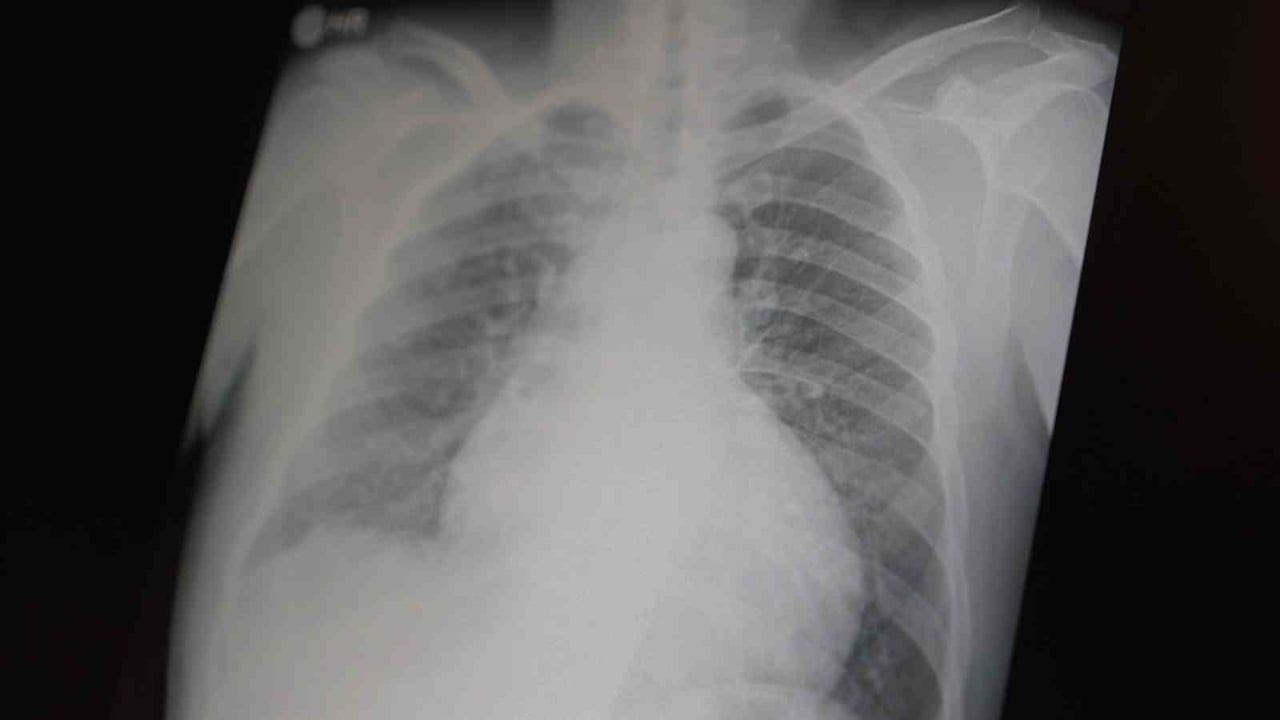

Her iki uyuşturucunun beyin hasarı yarattığını, ayrıca solunum ve kalp durmasına sebep olabileceğini vurgulayan Özkaya, "Metamfetamin, sadece küresel bir sorun değil, aynı zamanda ülkemizde de gençlerimizi etkileyen büyük bir toplumsal problem haline gelmiştir," şeklinde ifade etti.